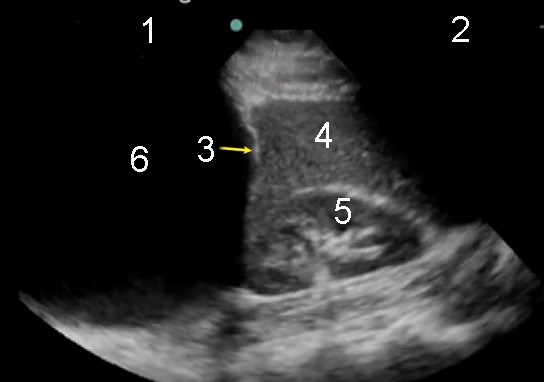

Toraconcentesis en derrame pleural grande con transductor en fase

1. Tórax superior

2. Abdomen inferior

3. Diafragma

4. Bazo

5. Riñón

6. Derrame pleural grande